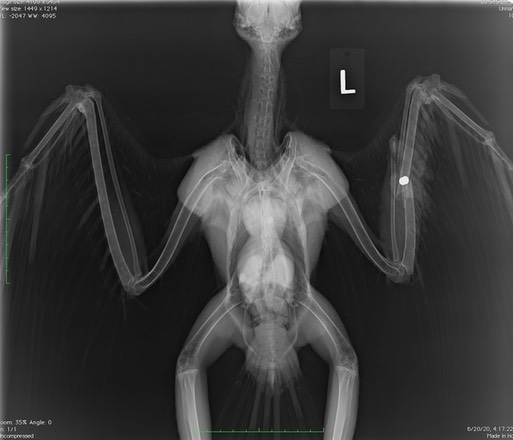

Swainson’s Hawk 20-315

Four days later, an adult female Swainson’s Hawk with a brood patch (indicating she had young in a nest) was admitted. She had a broken wing. A radiograph again confirmed she had been shot. The fractures in her left wing were not repairable and she was euthanized.